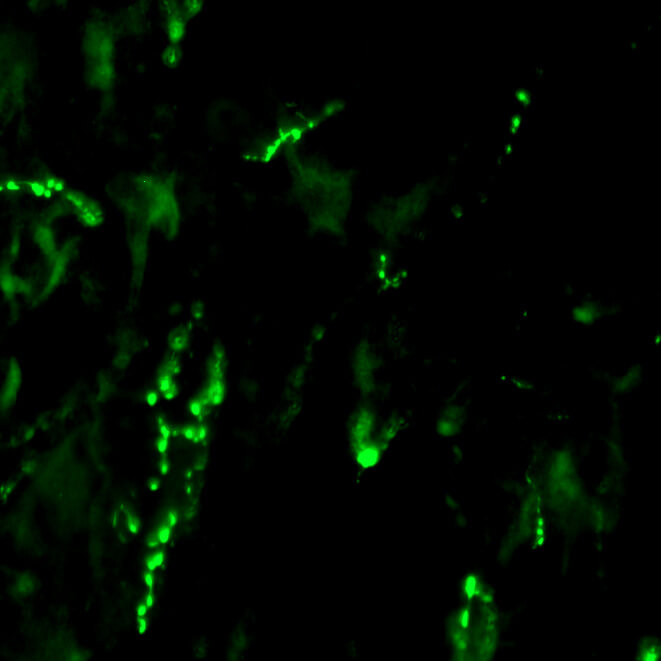

Physical therapy can improve both motor and sensory function after spinal cord injury, even at the chronic stage. Our group is studying optimal combination that can improve forelimb function after cervical spinal cord injury in a rat model. We are also interested in uncovering neural substrates that can mediate functional recovery in the chronically injured spinal cord.